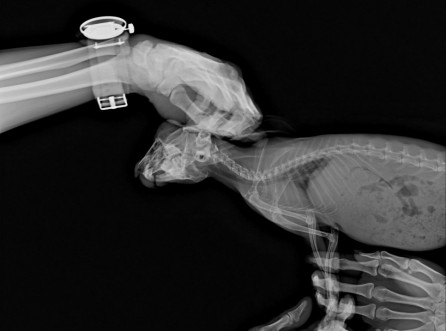

거북이, 이물섭취